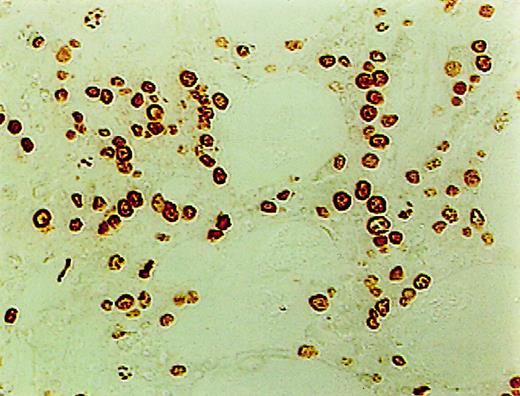

Measurement of apoptosis using ISEL

ISEL of fragmented DNA was performed on plastic embedded BM biopsies. A distinct brown staining in the nucleus identified a cell as being engaged in DNA cleavage. Among the 10 cases studied, 2 cases showed high positivity; 2, intermediate; 4, low; and 1, no ISEL positivity. When comparing MDS patients to the healthy donors, an increase in apoptosis was noted in MDS patients (3+ in MDS patients vs 0+ in donors; P = .1). All 3 lineages of hematopoietic cells, including the myeloid, erythroid, and megakaryocytic cells, were found to be undergoing apoptosis. Furthermore, in almost every case, stromal cells were also found to be apoptotic (Figure1).

High incidence of apoptosis involving hematopoietic and stromal cells in the BM of MDS patients using ISEL.

Brown staining is noted (original magnification × 400).